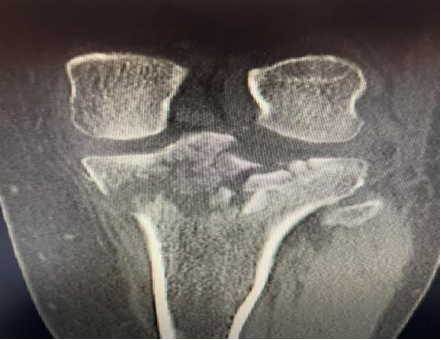

患者张女士(化名)因工作意外导致右膝受伤,影像检查结果显示:

右胫骨平台Schatzker V型骨折。这是胫骨平台骨折中最复杂、最严重的一种类型,其特征是:

▪️ 关节面粉碎性塌陷:膝盖的“承重面”支离破碎。

▪️ 干骺端与骨干完全分离:骨折线延伸至小腿骨干,稳定性完全丧失。

▪️ 常伴软组织严重损伤:皮肤、韧带、血管神经损伤风险极高。

(术前图)